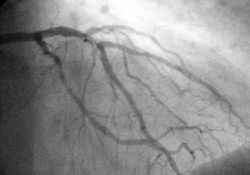

Coronary angioplasty

Percutaneous coronary intervention (PCI), commonly known as coronary angioplasty, is a therapeutic procedure to treat the stenotic (narrowed) coronary arteries of the heart found in coronary heart disease. These stenotic segments are due to the build up of cholesterol-laden plaques that form due to atherosclerosis. PCI is usually performed by an invasive cardiologist. Percutaneous coronary intervention can be performed to reduce or eliminate the symptoms of coronary artery disease, including angina (chest pain), dyspnea (shortness of breath) on exertion, and congestive heart failure. PCI is also used to abort an acute myocardial infarction, and in some specific cases it may reduce mortality.

Basically, in this technique, a wire is passed from the femoral artery in the leg (or, less commonly, from the radial artery or brachial artery in the arm) to beyond the area of the coronary artery that is being worked upon. Over this wire, a balloon catheter is passed into the segment that is to be opened up. The end of the catheter contains a small folded balloon. When the balloon is hydraulically inflated, it compresses the atheromatous plaque and stretches the artery wall to expand. At the same time, if an expandable wire mesh tube (stent) was on the balloon, then the stent will be implanted (left behind) to support the new stretched open position of the artery from the inside.

In coronary angioplasty, the angioplasty and stenting typically is performed through a thin flexible catheter during Cardiac Catheterization with just a local anaesthetic to the groin (or wrist) where the catheter was inserted, often making heart surgery unnecessary. While coronary angioplasty has consistently been shown to reduce symptoms due to coronary artery disease and to reduce cardiac ischemia, it has not been shown in large trials to reduce mortality due to coronary artery disease, except in patients being treated for a heart attack acutely (also called primary angioplasty). There is a small but definite mortality benefit (i.e., reduction) with this form of treatment compared with medical therapy, usually consisting of thrombolytic ("clot busting") medication.